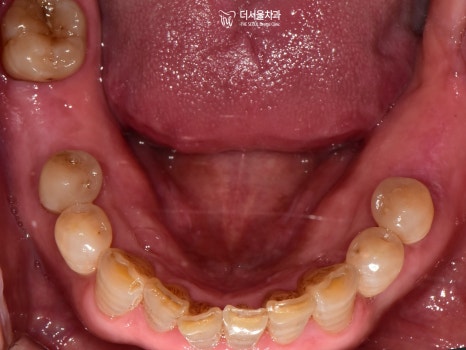

이제 결과를 보여드릴 차례네요.

모든 보철을 지르코니아를 사용하여

심미성을 한껏 더해주었습니다.

이렇게 몇 곳만 바뀌어도

가만히 있던 주변 치아들까지

좀 더 건강하고 활기차 보이지 않나요?